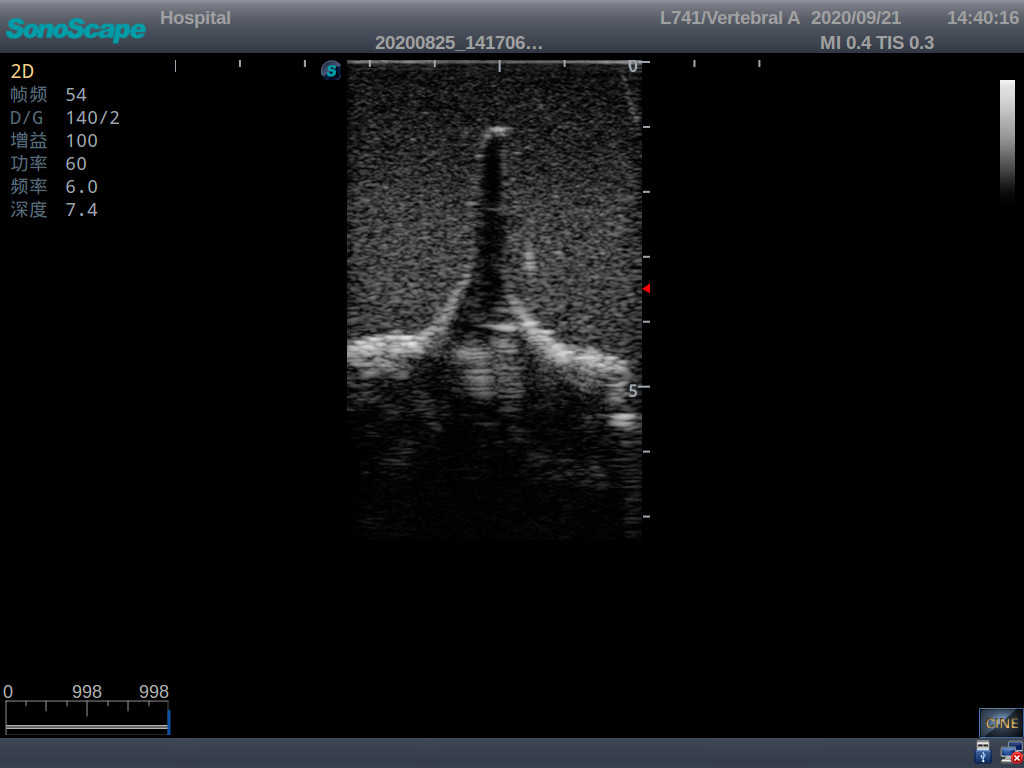

Adult Lumbar Puncture Ultrasound Training Model

Model TYE1549.2

This model is an ideal choice for ultrasound-guided adult lumbar puncture training with true-to-life skin feel and touch, accurate anatomical structures as well as real clinical ultrasound images. Realistic resistance to needle tips and correct landmarks provide excellent hands-on experience.

2)  Real clinical ultrasound images

3)  Compatible with various real ultrasound machines

1)   Ultrasound-guided lumbar puncture practice

2)   Resistance & “pop” felt through the needles